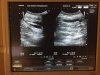

Густая кровь на курсе. Высокий гематокрит. Слив крови